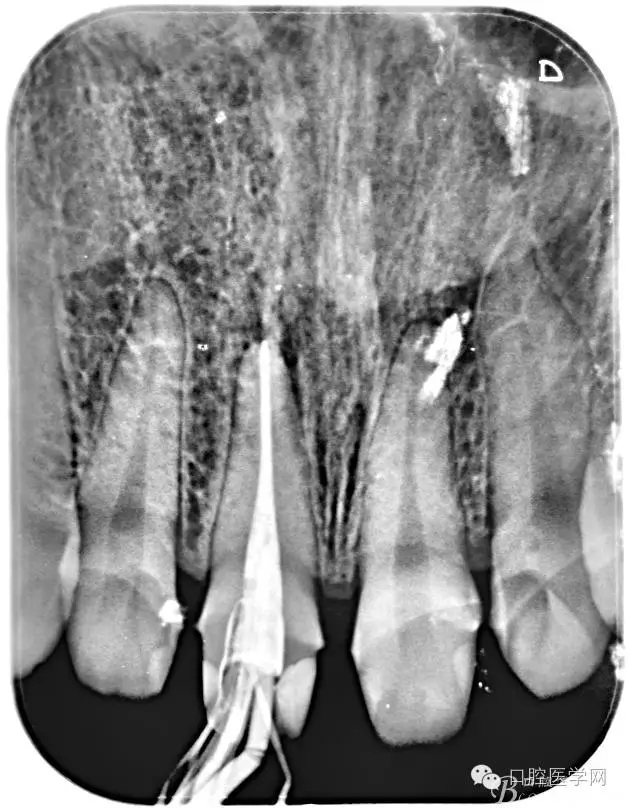

2、根管填充的界限

根管的解剖界限是从髓室根管入口到根尖部牙本质- 牙骨质交界处(生理性根尖孔) 。理想的根管充填应该是对生理性根尖孔冠方以上进行严密的三维封闭。临床上根据X线牙片判断根管充填的质量。牙片上充填材料与根管壁紧密接触一般被认为充填严密。关于充填止点,由于牙本质- 牙骨质界离根尖孔外表面平均距离为0. 5~0. 7 mm,同时相当多的根尖开口并不位于X线片的根尖处。因此临床上认为材料充填至距X线片牙根最尖端0. 5~1 mm (也有认为0. 5~2mm)为适填。